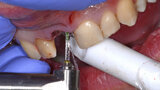

Fig. 1: Situation before treatment, which led to the decision to extract tooth #11.